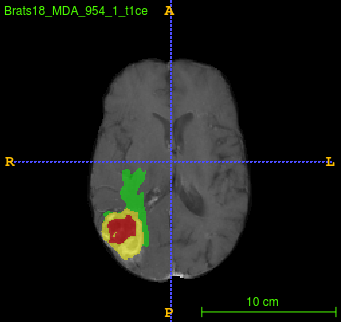

Segmentation of brain tumor from magnetic resonance imaging (MRI) is a vital process to improve diagnosis, treatment planning and to study the difference between subjects with tumor and healthy subjects. In this paper, we exploit a convolutional neural network (CNN) with hypercolumn technique to segment tumor from healthy brain tissue. Hypercolumn is the concatenation of a set of vectors which form by extracting convolutional features from multiple layers. Proposed model integrates batch normalization (BN) approach with hypercolumn. BN layers help to alleviate the internal covariate shift during stochastic gradient descent (SGD) training by zero-mean and unit variance of each mini-batch. Survival Prediction is done by first extracting features(Geometric, Fractal, and Histogram) from the segmented brain tumor data. Then, the number of days of overall survival is predicted by implementing regression on the extracted features using an artificial neural network (ANN). Our model achieves a mean dice score of 89.78%, 82.53% and 76.54% for the whole tumor, tumor core and enhancing tumor respectively in segmentation task and 67.90% in overall survival prediction task with the validation set of BraTS 2018 challenge. It obtains a mean dice accuracy of 87.315%, 77.04% and 70.22% for the whole tumor, tumor core and enhancing tumor respectively in the segmentation task and a 46.80% in overall survival prediction task in the BraTS 2018 test data set.